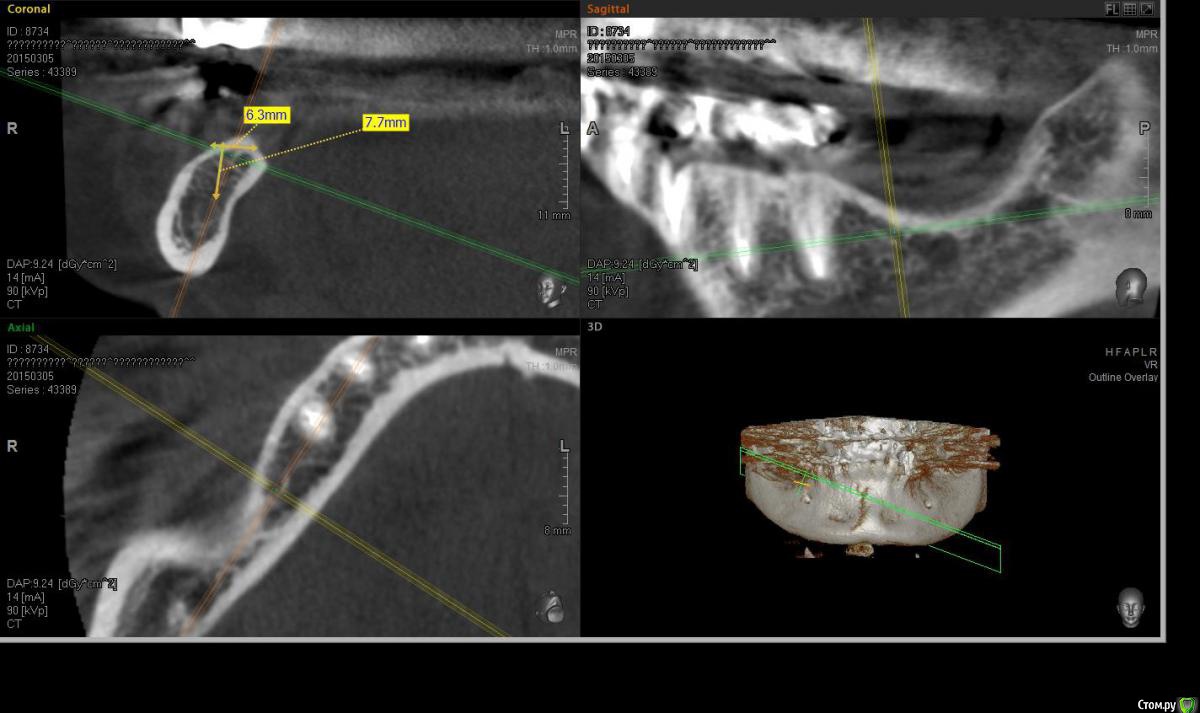

Acidrocker Опубликовано 14 марта, 2015 Поделиться Опубликовано 14 марта, 2015 Всем здравствуйте!Посоветуйте, пожалуйста, как тут лучше сделать? Ставить 8-ку с НРК? Или может как-нибудь двухэтапно, например нрк с каркасом или цитопластом? 1 Ссылка на комментарий

Acidrocker Опубликовано 28 марта, 2015 Автор Поделиться Опубликовано 28 марта, 2015 GBR c цитопластомТак и сделал. Кейс сделаю как будет готов) http://s018.radikal.ru/i524/1503/93/372d86216cee.jpghttp://s013.radikal.ru/i322/1503/0b/d569360733ef.jpg 2 Ссылка на комментарий